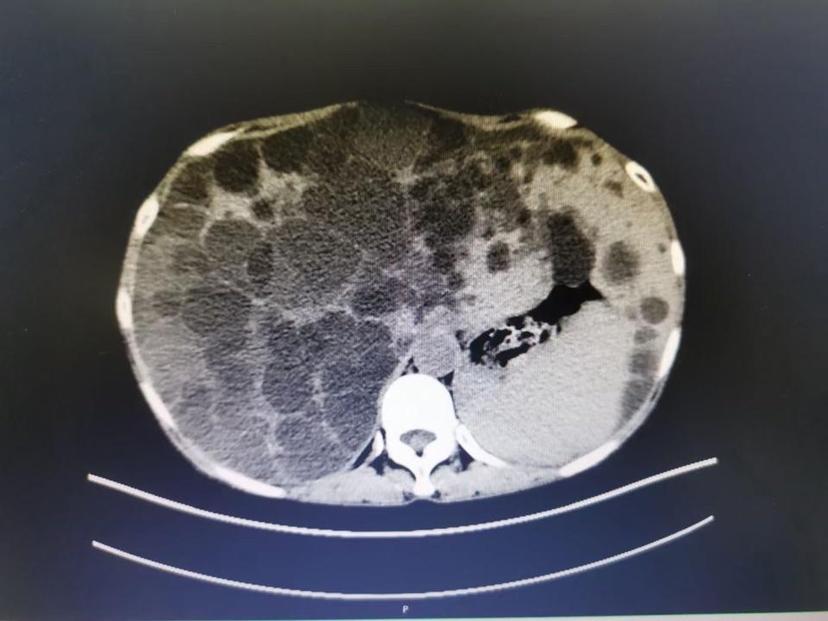

腹部ct读片之多囊肝和多囊肾

图片尺寸1728x1080